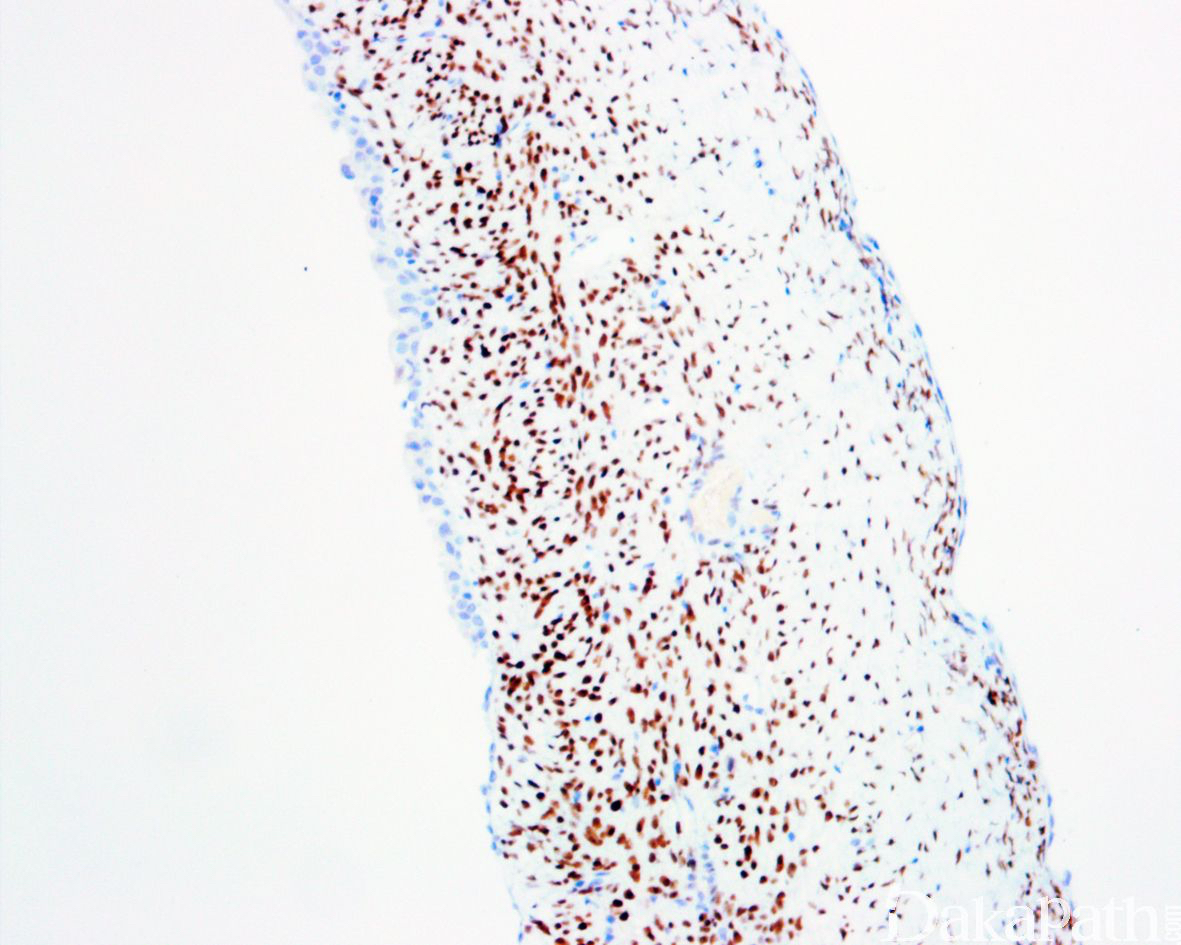

免疫组织化学染色:

上皮 PAX8 阳性,间质细胞 ER 阳性,Inhibin 阴性。